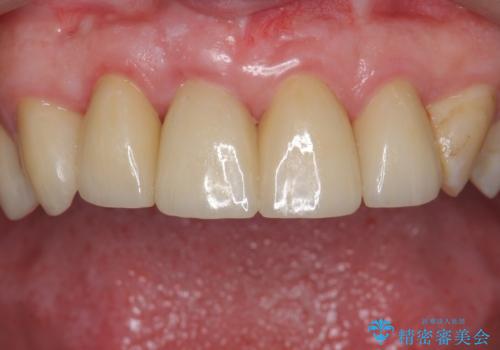

前歯の虫歯 つぎはぎの歯をセラミックに

- 前歯の被せもののやり直しを希望して来院。

隣の歯もつぎはぎでプラスチックが劣化していたため、虫歯を取りセラミックでかぶせました。

保険治療の前歯の被せものの縁(マージン)が歯茎の中まで及んでいたため、歯周外科手術を行い、マージンが歯肉縁下深くならないように設定しました。